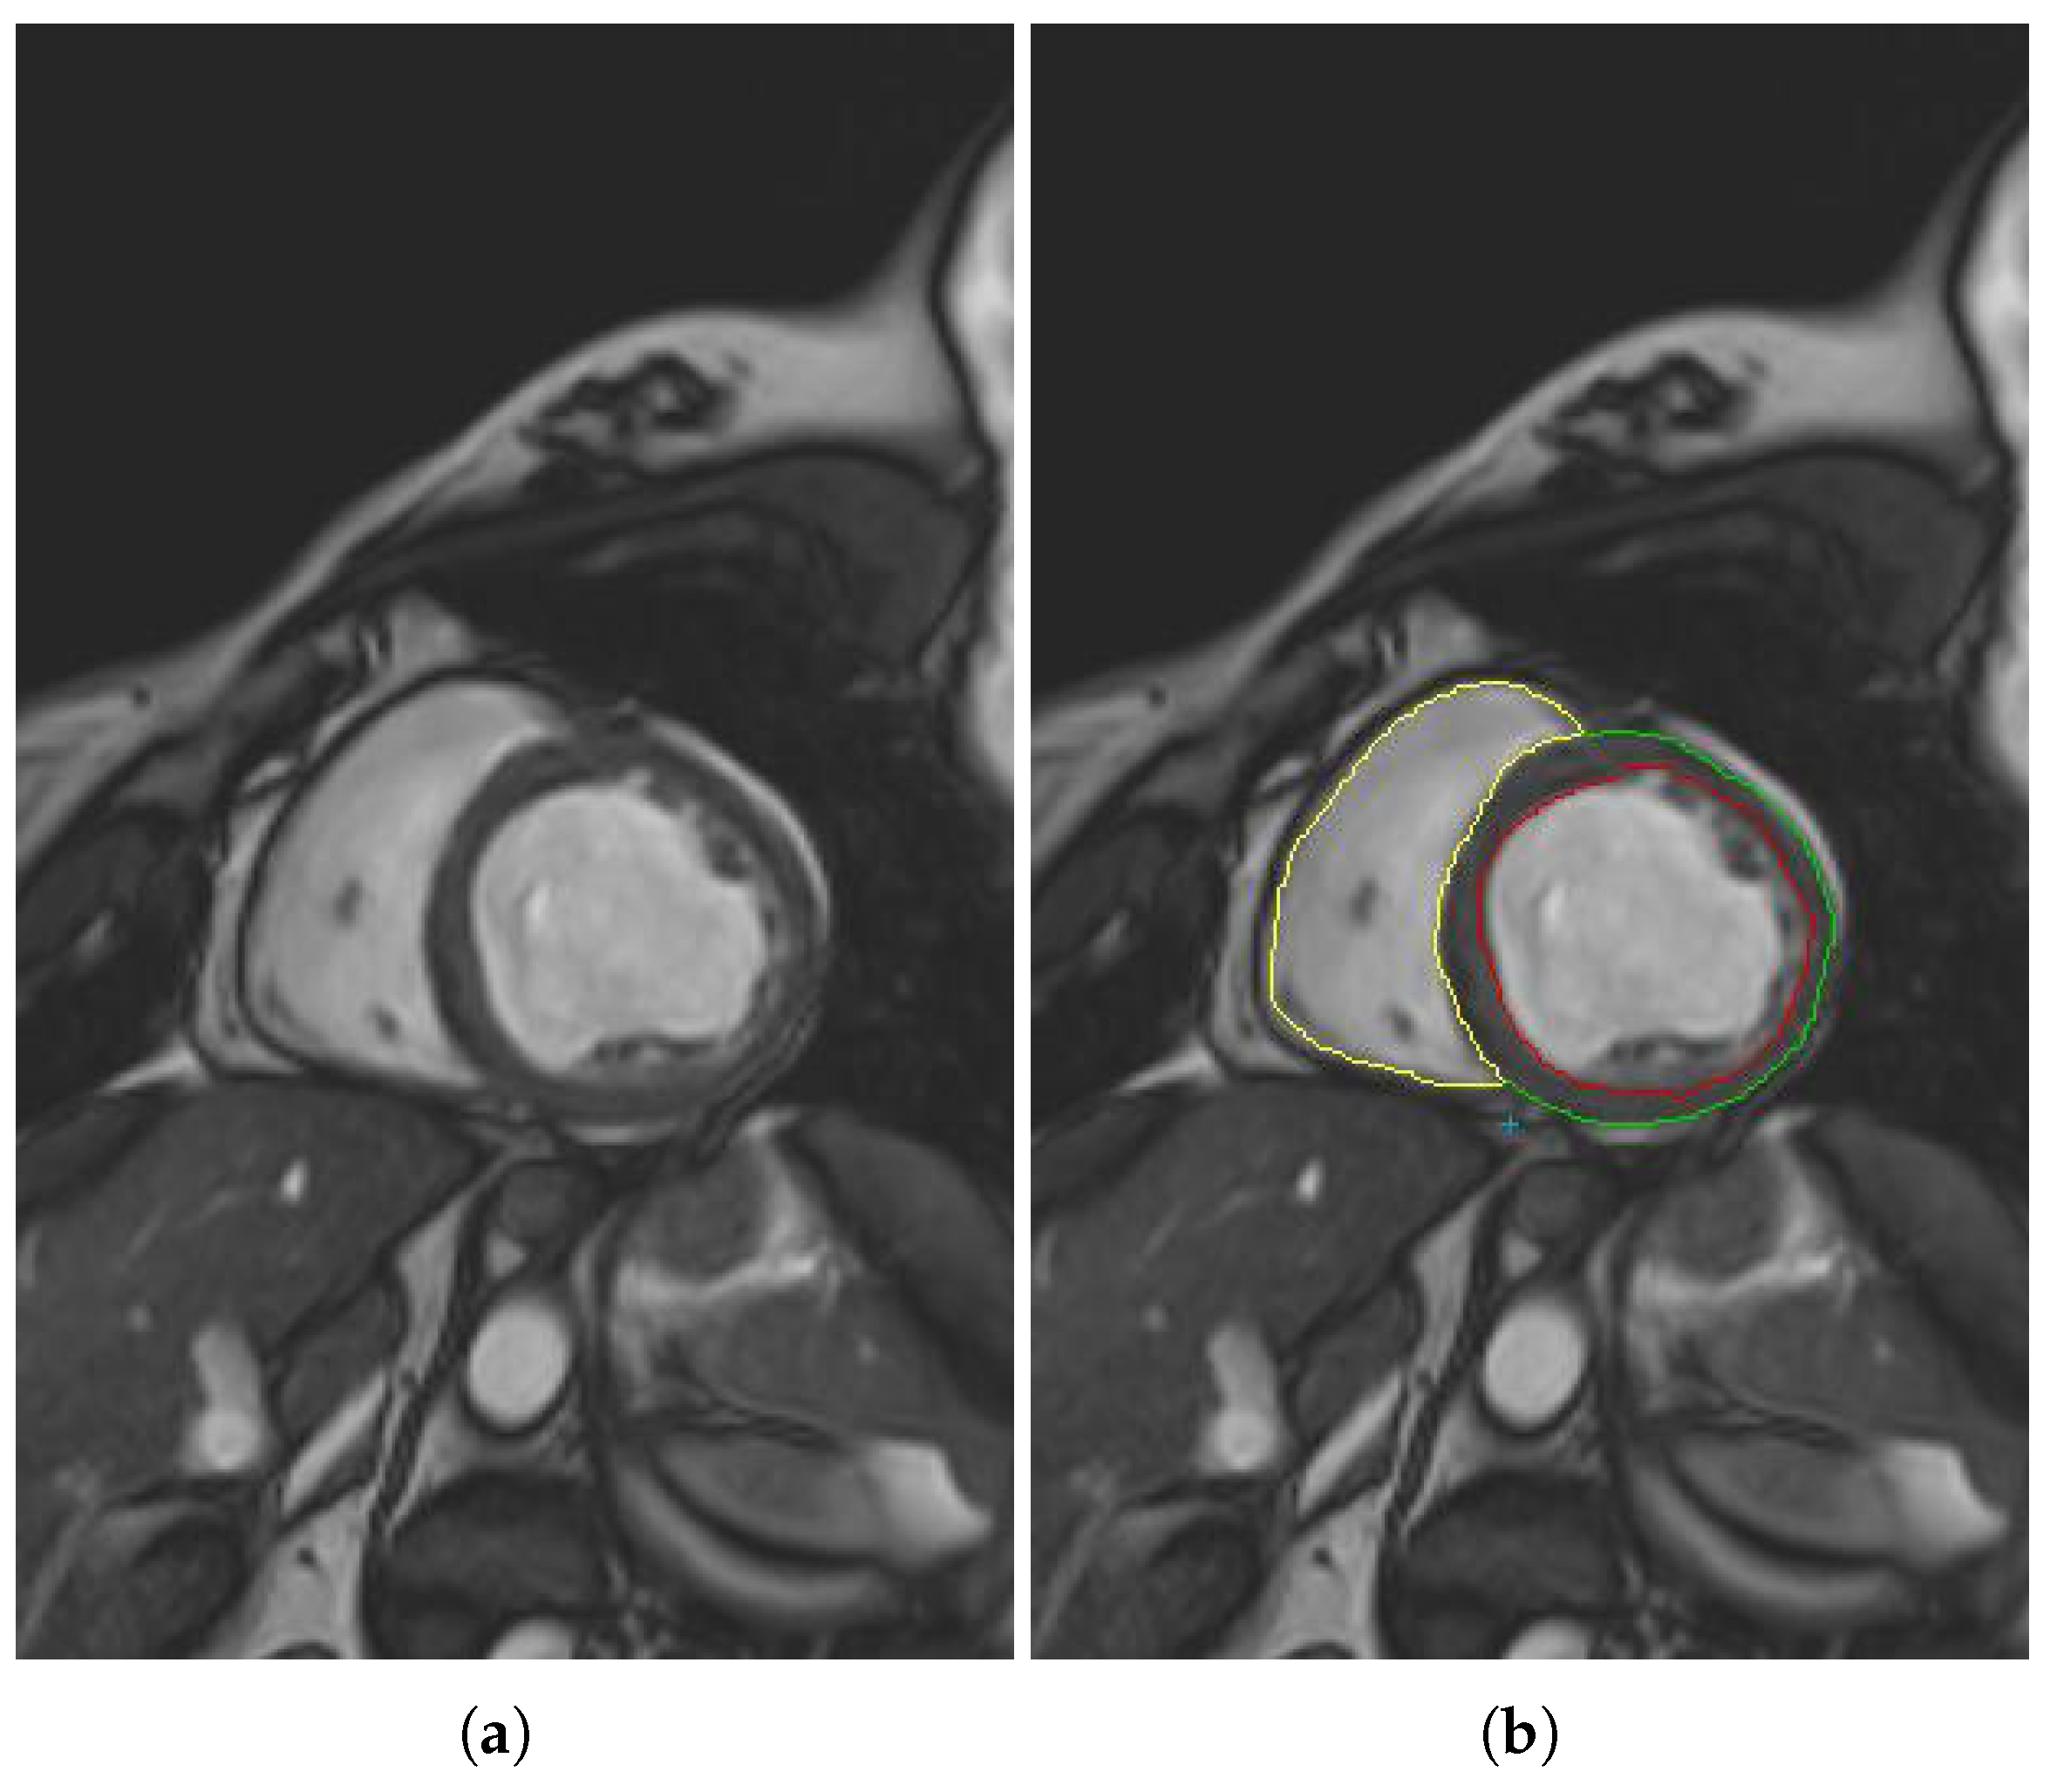

- The different MSERs are detected in a centered ROI of each input image by the use of OpenCV [23]. As the LV cavity is normally represented by a circular shape, the centroid of each MSER detected is computed in order to automatically identify the left ventricle cavity anywhere in the image and for applying the convex hull.

- The previous application of the convex hull allows a second refining to optimize the search process of the external layer and the trabeculae areas. The parameter e-expand is redefined and adjusted to accurately determine the external layer of the compact zone, thanks to plotting several lines from the centroid of the LV to reach the points of the external layer. This parameter establishes the distance of the lines between the centroid of the LV cavity and the possible space where the external layer can be found, taking into account the particular features of genetic cardiomyopathies. We optimized the parameter e-expand for different situations or possible cardiomyopathies.